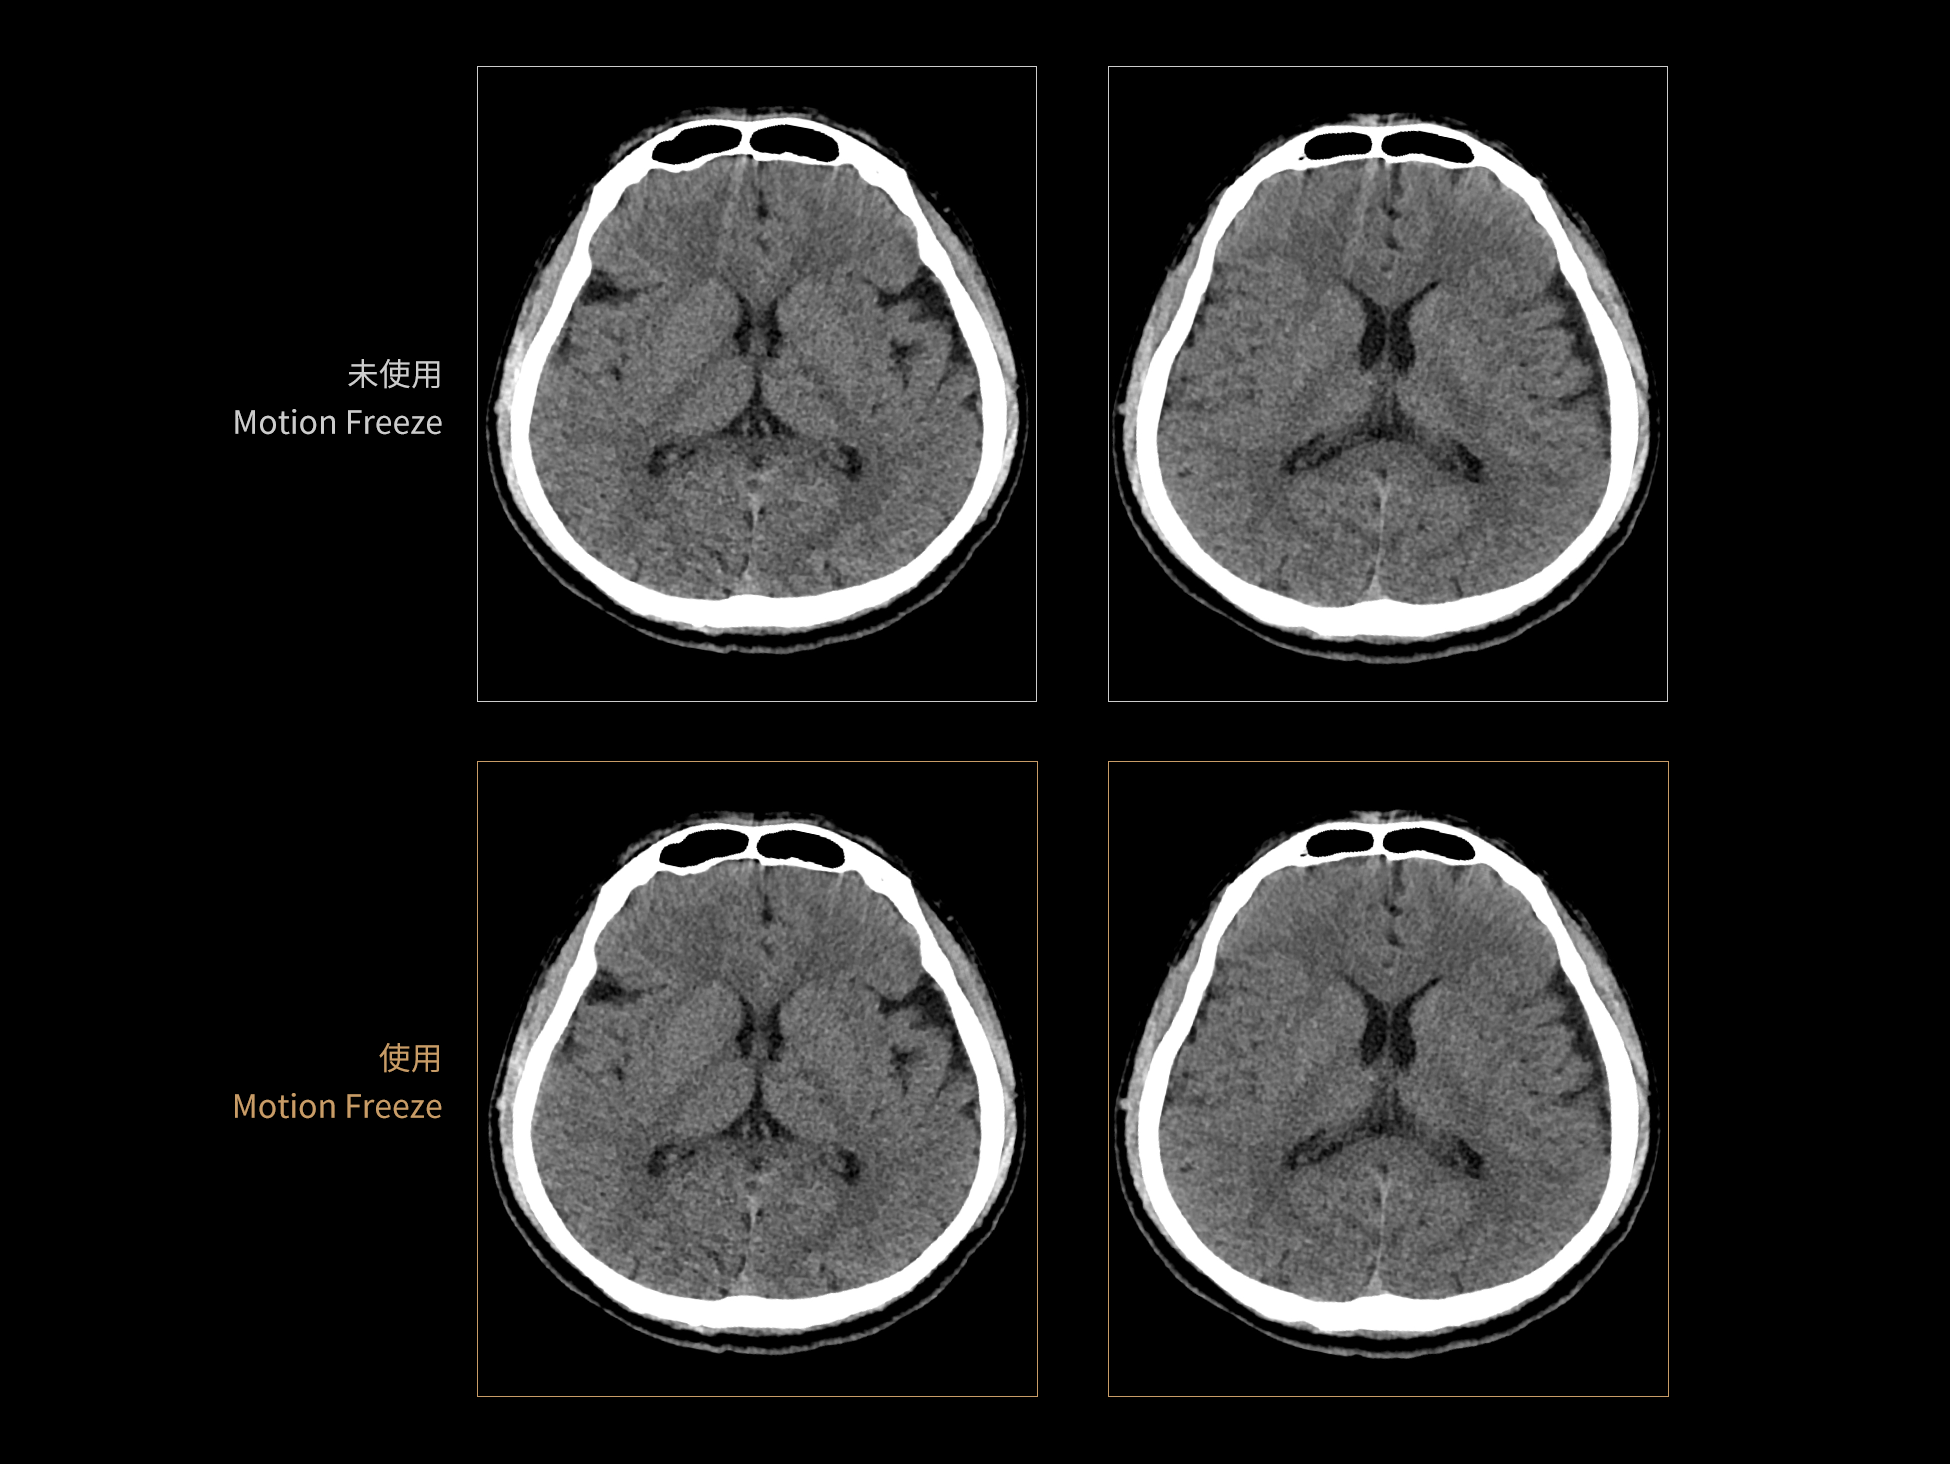

Motion Freeze: 深度学习头部运动伪影校正算法

Motion Freeze 有效抑制头部运动伪影,清晰呈现脑部结构与病灶信息,避免重复扫描,节省检查时间与资源,并降低患者辐射暴露。该算法适用于平扫、增强扫描、CTA 和灌注等多种头部检查模式,显著提升神经系统成像的图像质量与诊断准确性。

患者头部运动通常呈现多种运动模式,现有算法难以全面消除由此产生的伪影。为构建高质量的训练数据集,Motion Freeze算法在X、Y、Z三个方向上模拟旋转、平移、振荡及多种复合运动场景,系统生成多样化的运动伪影样本。通过引入丰富的运动干扰,该方法使网络模型具备更强的泛化能力,能够应对多种复杂的头部运动情况。

支持多种扫描协议下头部运动伪影抑制

三维建模解析真实运动状态